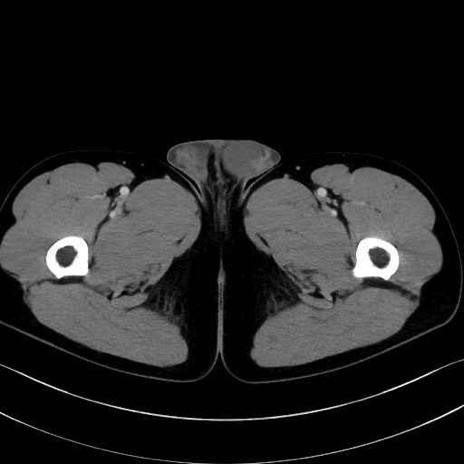

大腿方形筋(Quadratus femoris muscle)のCT画像の解剖

大腿方形筋 (Quadratus femoris)